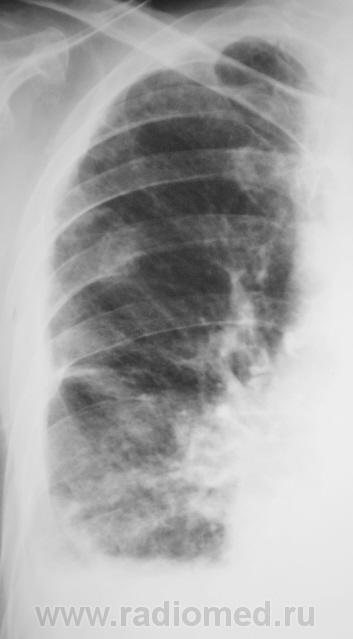

Пациент с подозрением на «пневмонию» направлен на рентгенографию ОГК.

Срыв компенсации в большом круге кровообращения. В верхней доле справа была тяжелая пневмония.

По-моему, здесь всего " до кучи"-застой в малом круге+ верхняя доля справа как-то напрягает.В синусах с 2-х сторон выпот.